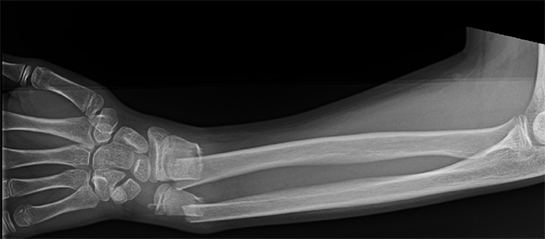

3. Damar Darlığı veya Tıkanıklığı Damarların daralması veya tıkanması, kan akışını etkileyerek çeşitli belirtilere yol açabilir. Bu durum, genellikle ateroskleroz gibi hastalıklardan kaynaklanır. Damar tıkanıklığı, damarın atışlarını etkileyebilir ve bazen ağrı veya rahatsızlık hissi ile birlikte olabilir.

5. Kardiyovasküler Problemler Kalp hastalıkları, yüksek tansiyon veya aritmi, damarlarda atış hissine neden olabilir. Bu tür durumlar, genellikle daha ciddi sağlık sorunlarının belirtisi olup, erken teşhis ve tedavi gerektirir.